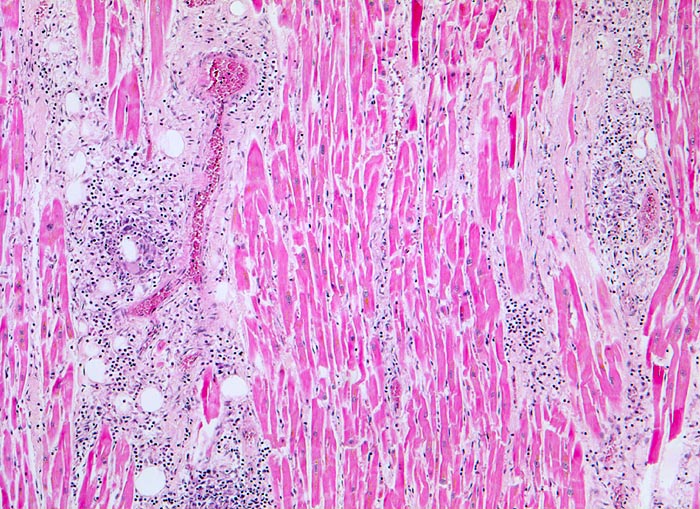

AP/ Aktive Myokarditis

Aktive Myokarditis

Bei etwa 30 bis 50% der Patienten mit vermuteter Myokarditis lassen sich bioptisch Veränderungen nachweisen. Wegen der herdförmigen Verteilung der Entzündung können beim Biopsieren Trefferfehler auftreten. Histopathologisch lassen sich in der ersten Biopsie eine akute (=aktive) und eine chronische Myokarditis unterscheiden. Bei beiden findet sich ein diffuses, fokales oder konfluierendes Entzündungsinfiltrat quantifiziert durch Immunhistochemie (>14 Lymphozyten und Makrophagen/mm2) und eine Fibrose. Bei der aktiven Myokarditis sind zusätzlich obligat Nekrosen oder eine Degeneration von Herzmuskelzellen nachweisbar.

• Teils fleckförmiges, teils diffuses gemischtes Entzündungsinfiltrat aus Lymphozyten, Plasmazellen, Makrophagen und zahlreichen eosinophilen Granulozyten.

• Einzelne Herzmuskelzellen werden durch das Entzündungsinfiltrat zerstört und sind hypereosinophil (Myozytolyse).

• Interstitielles Ödem (Auflockerung des Gewebes).

• Fleckförmige Fibrose.